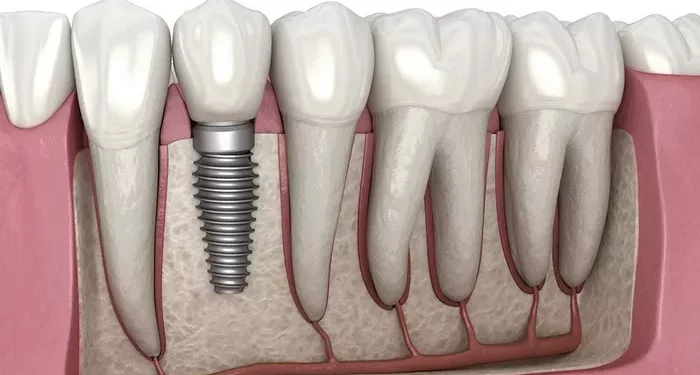

The New Jersey-based dental practice said the expansion comes in response to rising demand for full-arch dental restorations and coordinated implant care in Northern New Jersey. Full-mouth dental implants are designed to replace most or all missing teeth by securing a fixed restoration to implants placed in the jawbone.

Treatment for full-mouth dental implants typically includes diagnostic imaging, surgical implant placement, and restorative procedures, often completed over several appointments based on individual patient needs.

The Woodcliff Lake office uses diagnostic technologies such as cone-beam computed tomography (CBCT) to assist with implant planning and case evaluations. CBCT imaging helps clinicians assess bone structure and make informed implant placement decisions.